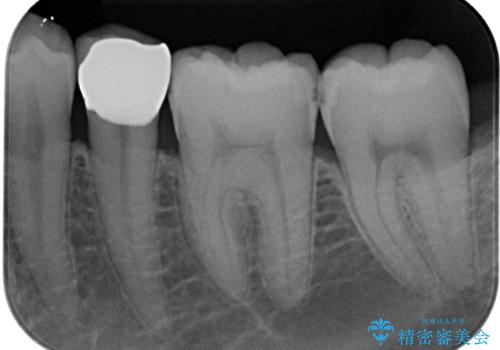

歯と歯茎の間に圧排糸と言われる糸を入れてシリコーン印象材にて型どりをしました。

フロスがちぎれることもなくなり、被せものが入っていることを忘れていたと大変喜んでいただきました。適合の良い被せものは二次的な虫歯の再発リスクを低減してくれます。